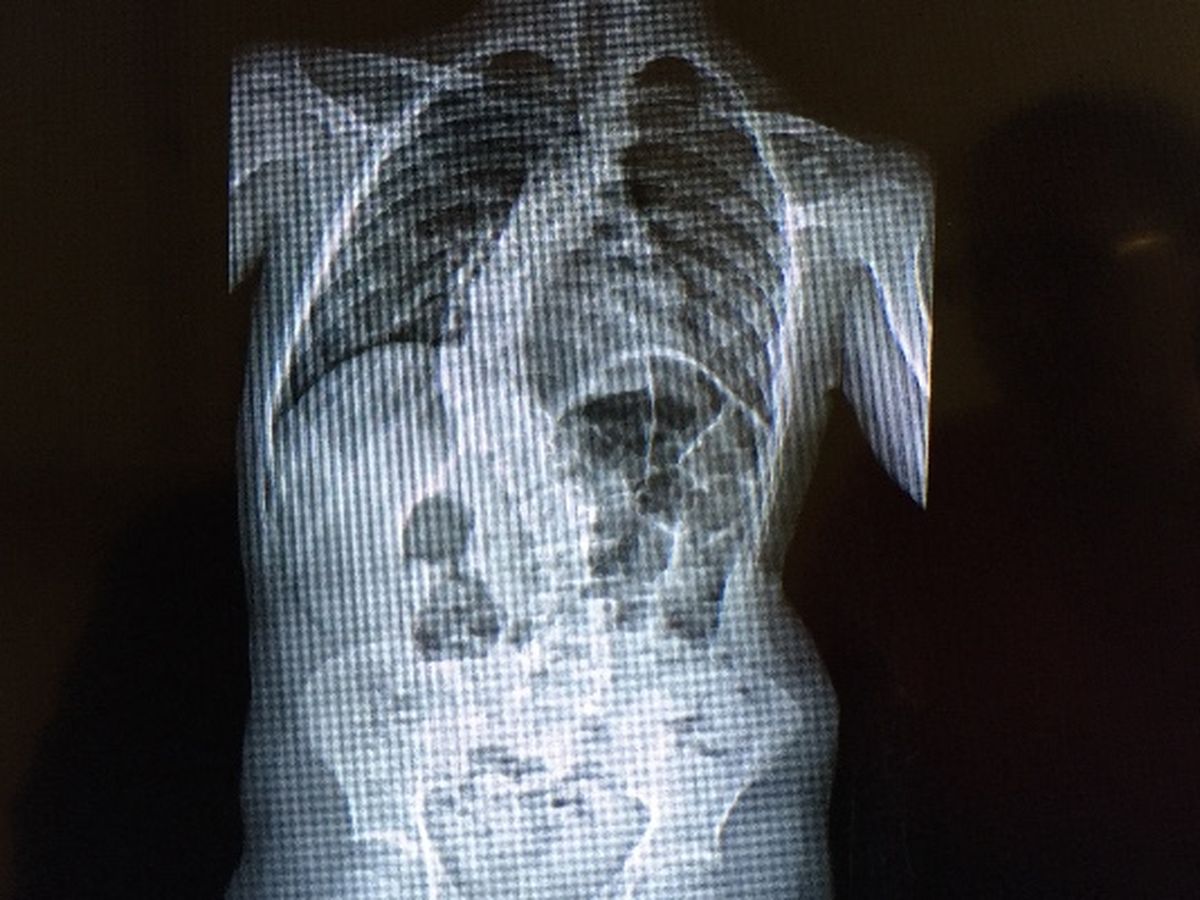

I am a single mom to a wonderful 15 year old special needs teenager. He is the most important person in my life. On July 5, 2016 I took Jared to his what was suppose to be a normal yearly wellness visit with his pediatrician. I was told he needed to see a Scoliosis specialist because he had a curve in his spine measuring at 17 degrees. At that time we were told they would probably take a x-ray and closely monitor him. The closest appointment I could get was for Thursday, July 28, 2016. While at the appointment we were told the curve had progressed to a 60 degree curve and he would need surgery. Sooner rather than later. I felt like my world had just turned upside down. My heart was crushed. It got even worse when the doctor said he was concern that due to Jared's medical issues from birth (pelvic kidney and motor tics) there might be something tethered in his spine. They sent Jared to have 3 MRIs and 2 CTs on Thursday, August 4, 2016. Well on Tuesday, August 9th we finally received some good news. There is nothing tethered in his spine! Our heavenly father heard our prayers! Thank you all for your prayers. Now since nothing is in the spine they can proceed with the surgery to correct the curve. Due to Jared's spine not being as flexible as they would have liked they will only be able to correct it to a 20 and hold it there. This is a lot better than the 60 degrees that it is currently. If this surgery is not done soon and the curve progresses to a 75-95 Jared would most likely start to develop breathing problems and at 95-110 he could start developing heart problems. We do not want this to happen so surgery has been scheduled for Thursday, September 8, 2016. His recovery time is expected to be 6 weeks which will include in home physical therapy and hopefully home bound school. Many people have asked how they can help me financially during this time as my ability to work will be limited. Suggestions have been made that I setup this account. The money donated will go to paying for rent, electricity and other necessary living expenses as well as medical bills. No donation is to small. Thank you all for your help and support.